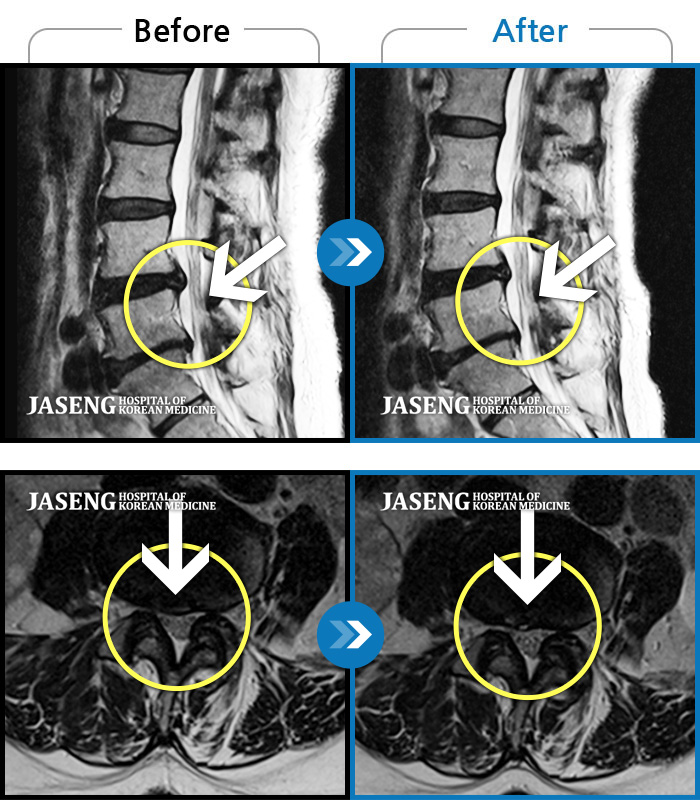

MRI ũ ʸ Ȯϼ.